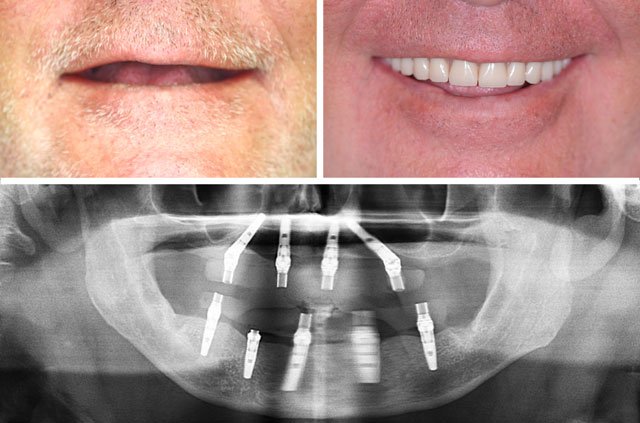

All-on-4 and immediate implant solutions for complete smile restoration. These cases showcase our expertise in full-arch rehabilitation with same-day teeth, providing patients with immediate functional and aesthetic results.

Same-Day Teeth

Walk in with failing teeth, leave with a complete, functional smile the same day

Natural Aesthetics

Custom-designed teeth that match your facial features and provide a natural appearance

All-on-4 is a revolutionary dental implant technique that uses just four strategically placed implants to support a full arch of replacement teeth. The posterior implants are angled at 30-45 degrees to maximize bone contact and avoid anatomical structures like the maxillary sinus or inferior alveolar nerve. This innovative approach allows for immediate loading with a temporary prosthesis, providing same-day teeth and eliminating the need for lengthy healing periods between procedures.